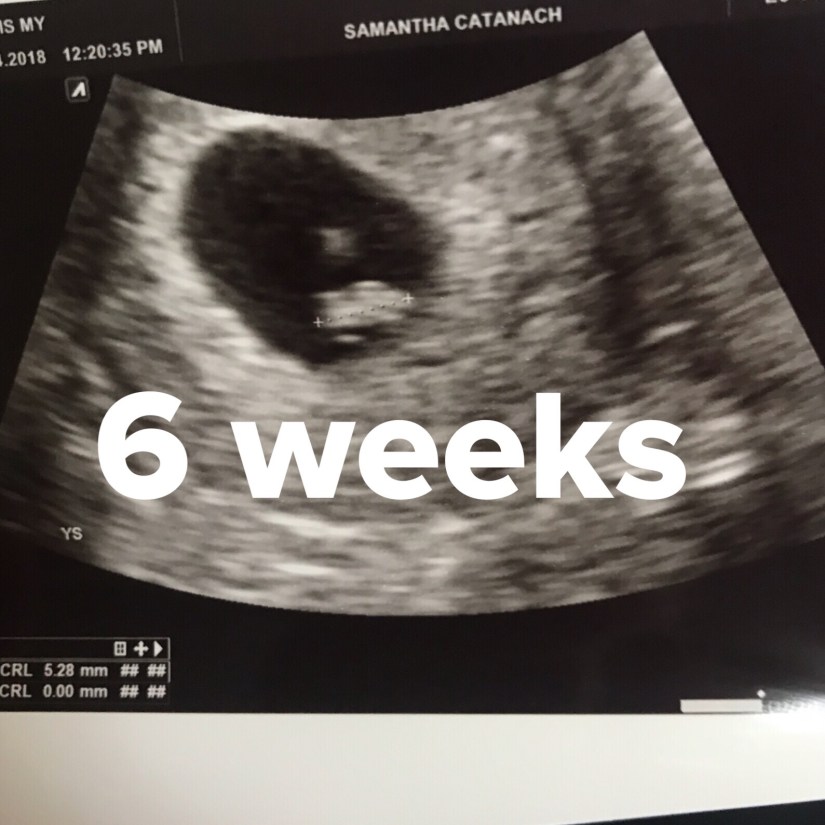

So at 6+2 I went along to the private scan, my legs were like jelly walking in the room I was terrified it was already over. I had filled in a form about my history so I think the sonographer knew how nervous I was. She said she wanted to do it abdominally and I felt immediately freaked out as I’ve only ever had an internal scan. She put the gel on my tummy and started looking around and I could see a tiny sac on the screen but it looked really small and my heart sank, I thought I was going to vomit.

She said shall we have a look internally but I think it’s looking good, I don’t think I’ve ever taken my knickers off so fast in my life ha ha. As soon as she started the internal scan I could see the sac and it looked much bigger and I could see a white blob in the sac. I said is that a baby and she didn’t say anything back, then all of a sudden the sound of a heartbeat came out of the speakers and filled the room. I just burst into tears repeating over and over again have I got a baby? Have I got a baby?

The answer was yes, a tiny little 5mm baby with a little heart beating away. When I had the photos in my hand it felt so precious, a tiny little blob, but right now it was my blob, it was ok and it was trying, fighting for me to be a mummy.